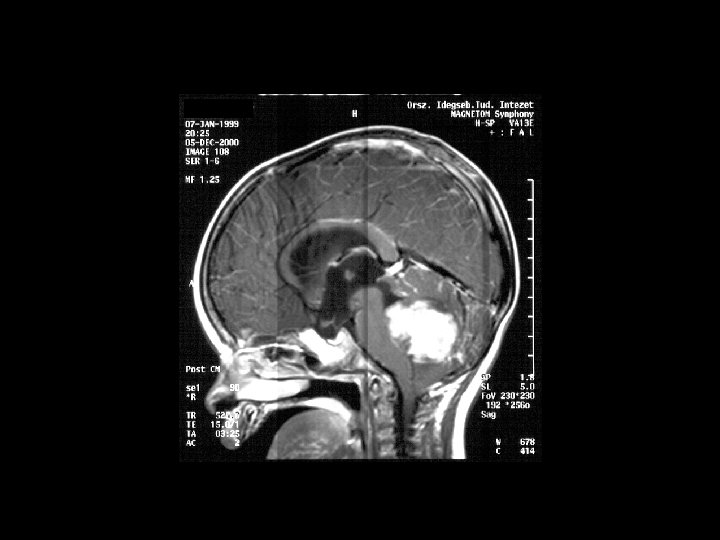

Diagnosis • essential: THINK OF IT ! • thorough neurological examination • MRI (brain+spine) • Opus – histology • CSF sampling

Histology based on localization • Supratentorial: astrocytoma (A 1 -4) (50%) PNET ependymoma • Infratentorial: astrocytoma (A 1 -2) (35%) medulloblastoma ependymoma (E 1 -3) • Brainstem: (15%) astrocytoma (A 1 -4) • Pineal region : germ cell tumors PNET